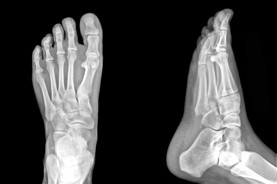

Alberta Plantar Fasciitis & Foot Pain Specialists

The Foot Institute is an association of Alberta Doctors specializing in the medical treatment of the foot and ankle, and is one of the largest groups of foot specialists in Alberta.

The Alberta Foot Institute is dedicated to the medical and surgical treatment of the foot. Our mandate is to provide the best possible medical, surgical and preventative treatment available for our patients. We do this by providing well-trained Doctors who are committed to treat and prevent all types of foot pain, biomechanical disorders, as well as all other problems relating to the feet.

At the Alberta Foot Institute, our Doctors are trained to specifically treat problems associated with your feet or ankles. Below are several of the most common problems that we see on a day to day basis: